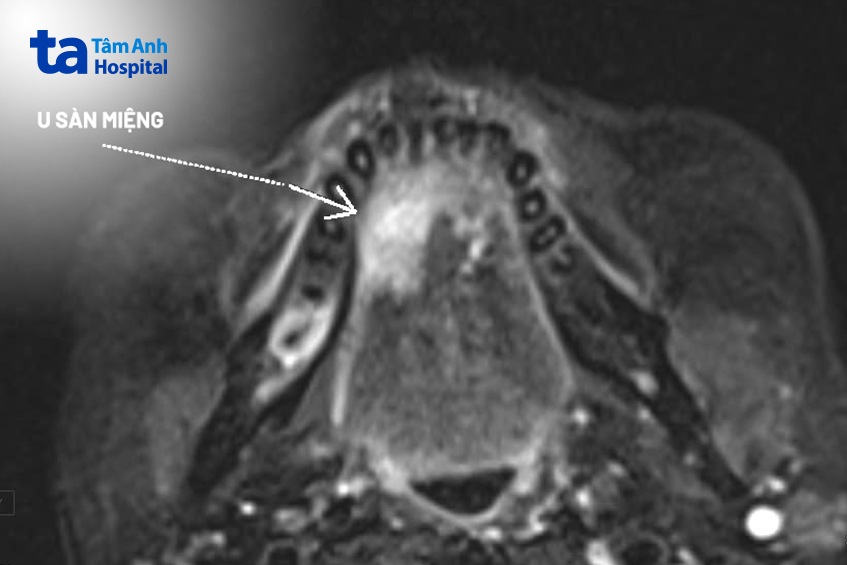

Ông Hùng (ngụ tại Thái Nguyên) có cảm giác đau trong miệng suốt hơn 1 tháng, điều trị tại địa phương không khỏi. Tại Bệnh viện Đa khoa Tâm Anh Hà Nội, bác sĩ chẩn đoán ông có khối u ác tính, sùi loét nằm ở mặt dưới lưỡi bên phải, kích thước 2x3cm. Kiểm tra bằng chụp cộng hưởng từ cho thấy khối u lan qua thắng lưỡi sang bên trái, vùng góc hàm bên phải có hạch kích thước 0,9×1,1cm. Tổn thương xâm lấn tuyến nước bọt dưới hàm bên phải, gây giãn ống tuyến, dính với phần lợi phía sau xương hàm, chân răng.